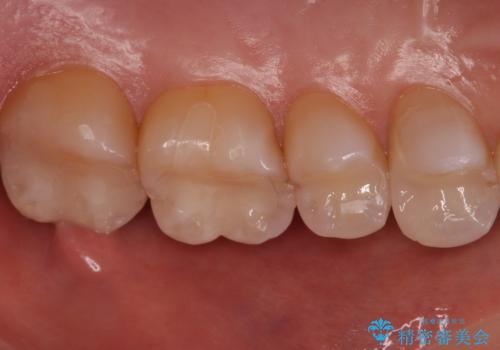

銀歯と樹脂の詰め物のやり替え セラミックインレーでの治療

- 奥歯の詰め物のやり替え希望で来院されました。

残る歯の量が多かったためすべてインレーでの治療となりました。

笑った時にチラついていた銀歯がなくなり大変喜んでいただけました。

セラミックは樹脂よりも変色しにくいため見た目が気になる方には特におすすめです。